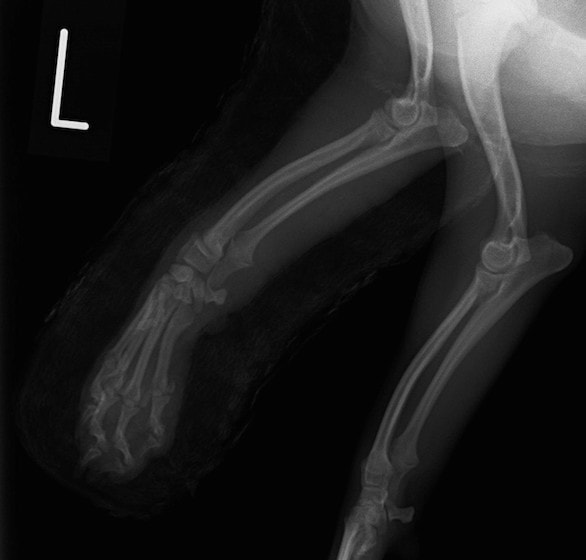

症例3:キルシュナーワイヤーのピンニングによる整復

ペルシャ猫 11ヶ月齢 雄

他院にて左大腿骨遠位の成長板骨折(salter-harrisⅠ型)が認められており、治療相談を目的として来院。当院にて、キルシュナーワイヤーを用いたピンニングにより骨折部位の整復を行いました。術後の経過は良好で、現在も経過観察中です。

術前レントゲン

術後レントゲン

Arthrex社のターゲティングデバイスを用いてピンニングの位置を調整することで、確実な固定を行っています。当院ではこの手術器具以外にも、人の手術にも使用される様々な器具を導入し、手術精度を高め、また医療メーカーと新しい器具の開発、試作にも取り組んでおります。